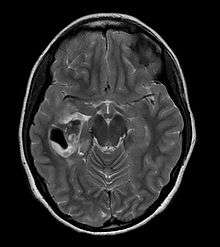

- A CT scan of the brain, and/or an MRI scan of the brain and spine, will be performed. A special dye may be injected into a vein before these scans to provide contrast and make tumors easier to see.